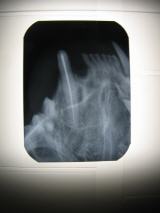

- Hochauflösendes digitales dentales Röntgen